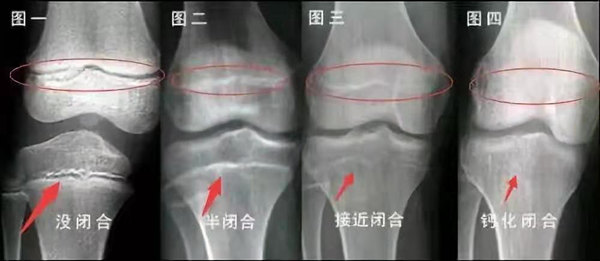

未成年時(shí)隨著年齡的增加骺軟骨端不斷骨化,骨骼就不斷增長(zhǎng)。當(dāng)骨骺線完全閉合時(shí)骨骼就停止生長(zhǎng),個(gè)子也就不再增長(zhǎng)了。一般骨骺端完全閉合的年齡是18~20歲左右。

一般來(lái)說(shuō),女孩的骨齡超過14歲,男孩的骨齡超過16歲,這時(shí)其骨骺線已接近閉合,基本沒有長(zhǎng)高的機(jī)會(huì)了。